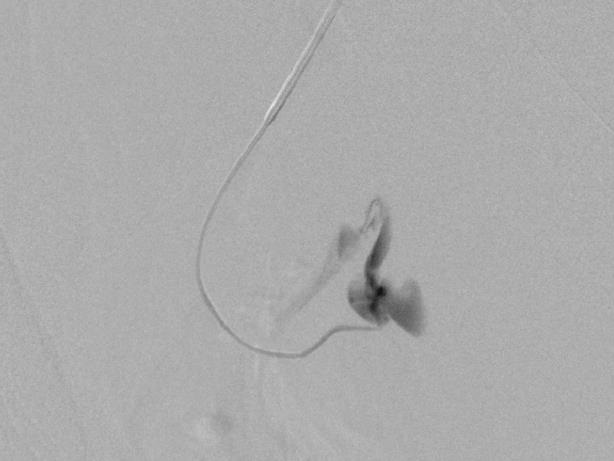

末端动脉栓塞:医源性肾损伤-移植肾活检

活检后动脉瘤破裂 |

微导管在载瘤动脉末端 |

载瘤动脉末端栓塞 |

Coil=3 |